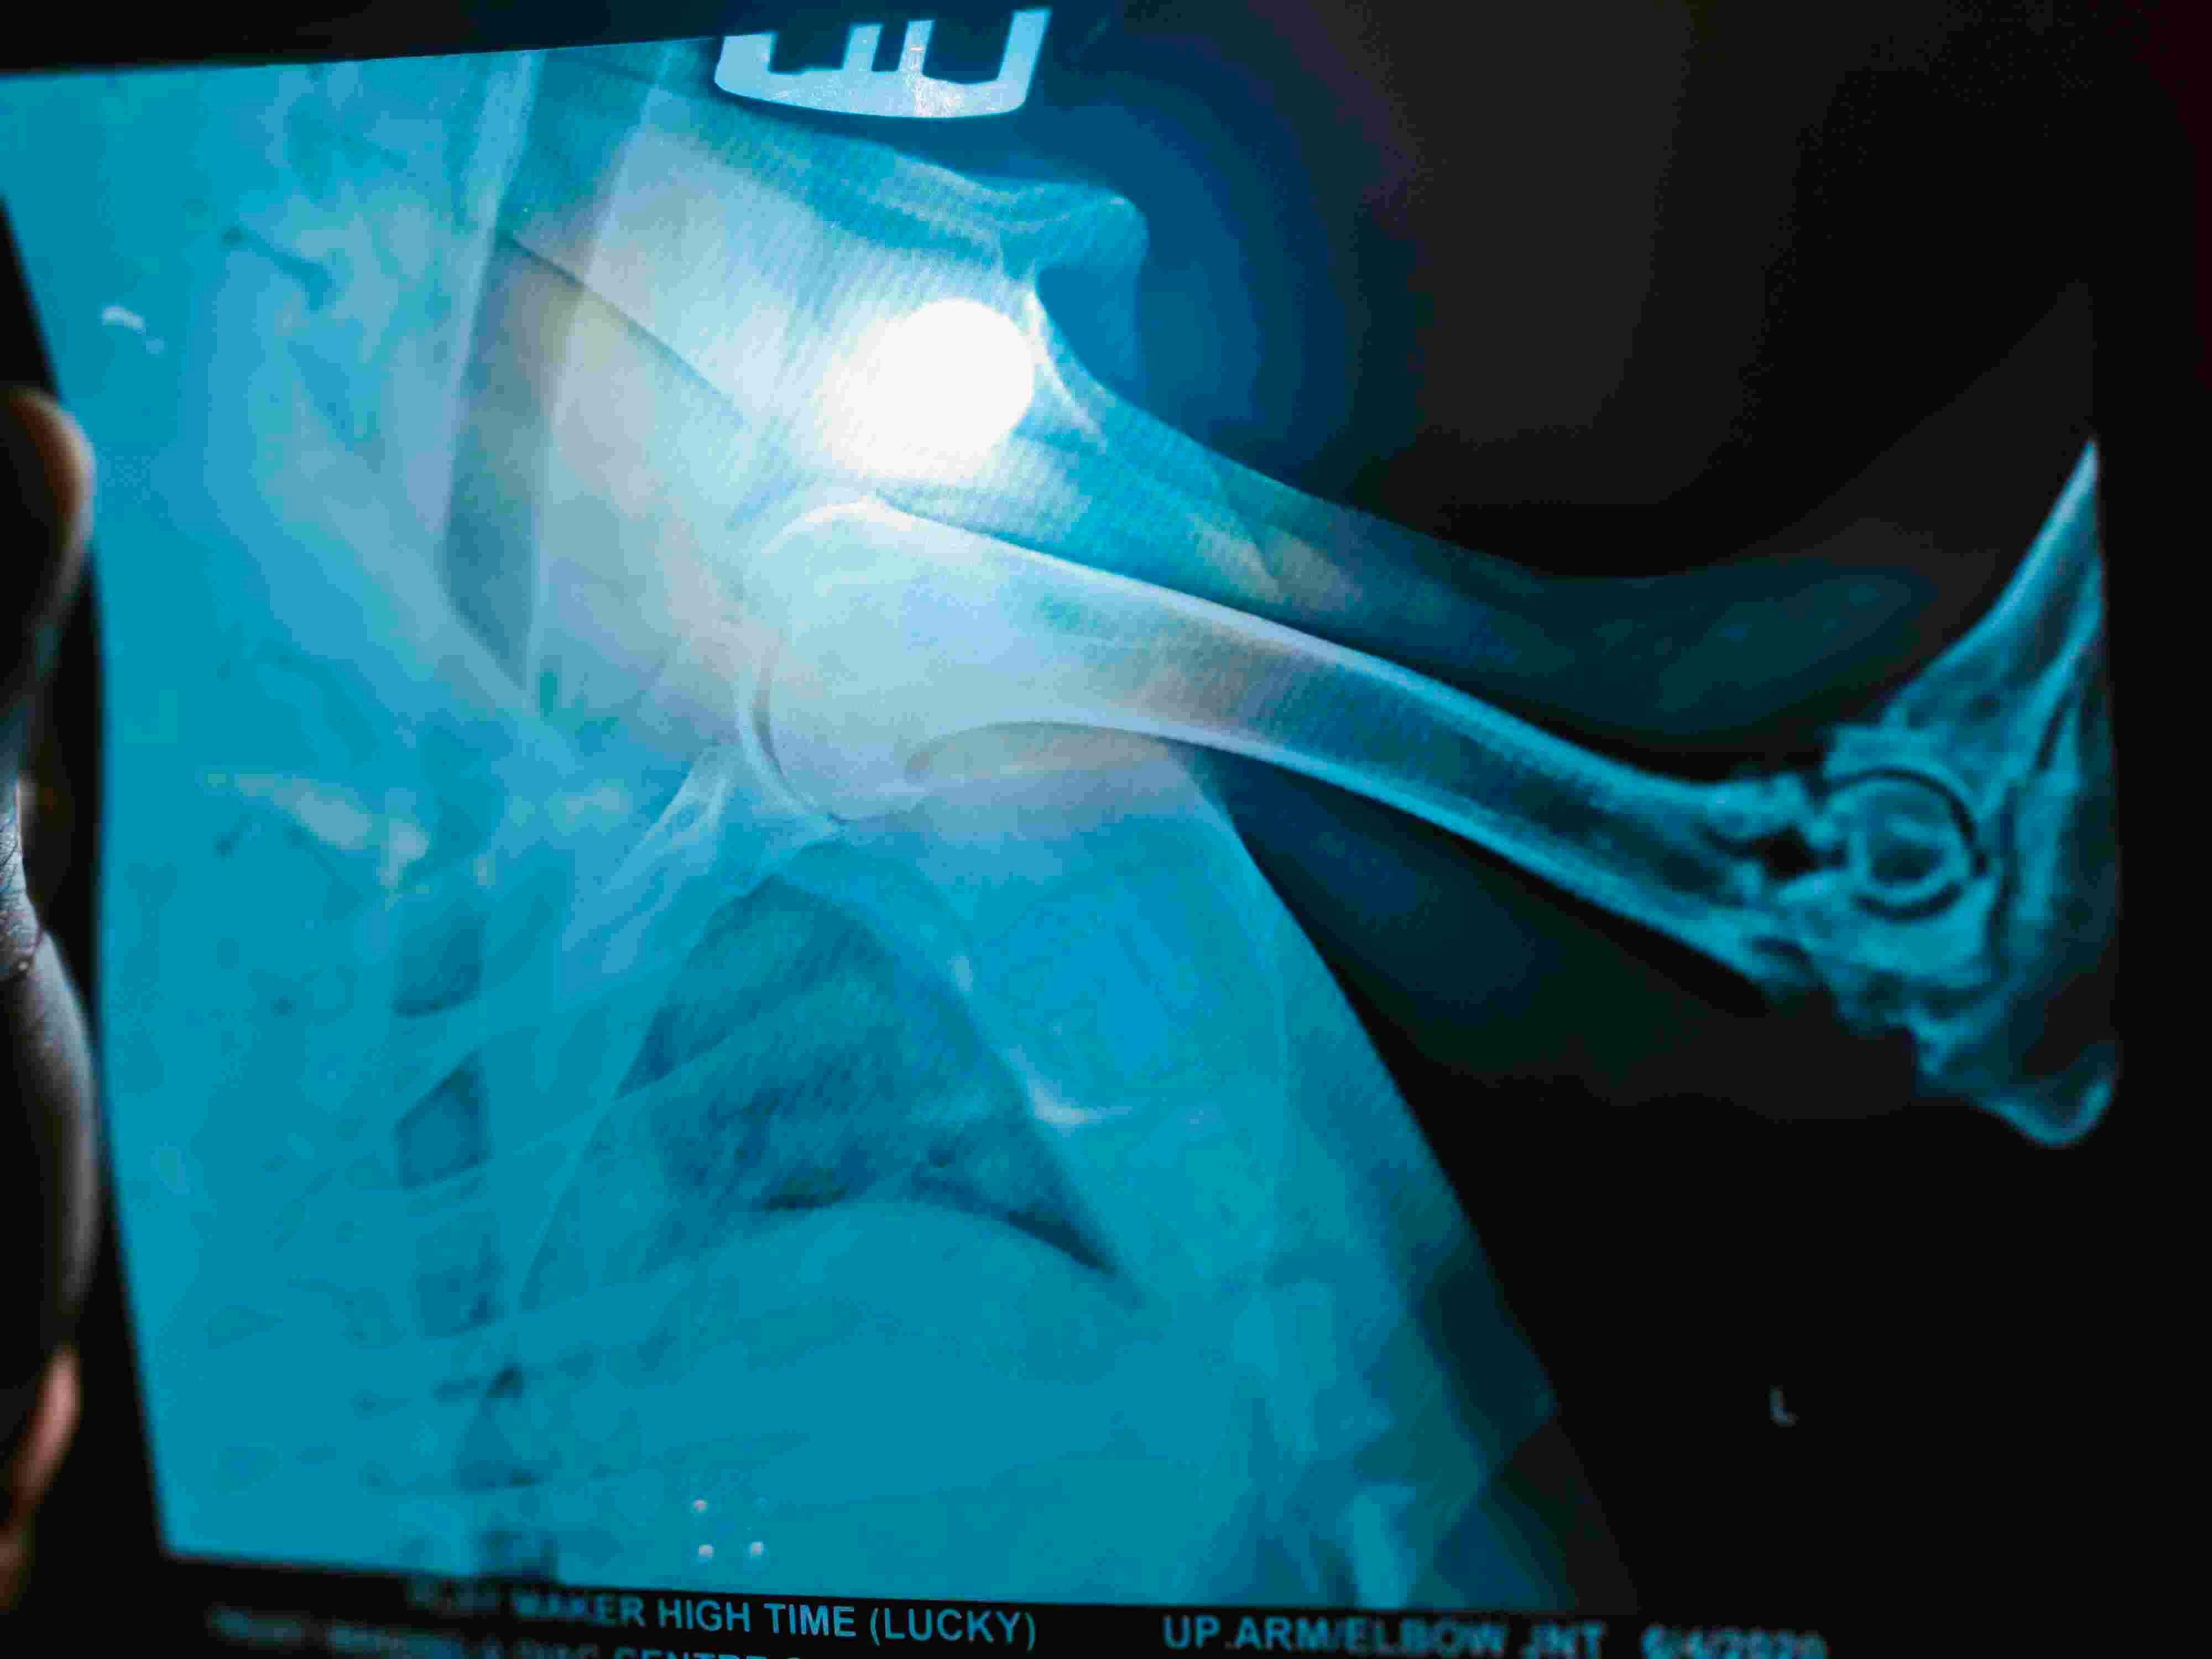

I am having a little trouble determine what is going on in the elbows. It looks like they are both fractured if these are pictures of different legs. The pelvis is also fractured. Treatment options would depend on the current condition of the pet and the cause for the injuries. Pelvic fractures often heal with strict cage rest for 1-2 months. The fracture of the elbow appears to have affected the joint, and it likely needs surgery to fix or amputation of the leg. If it is in both legs, surgery to fix the fractures is the best option.